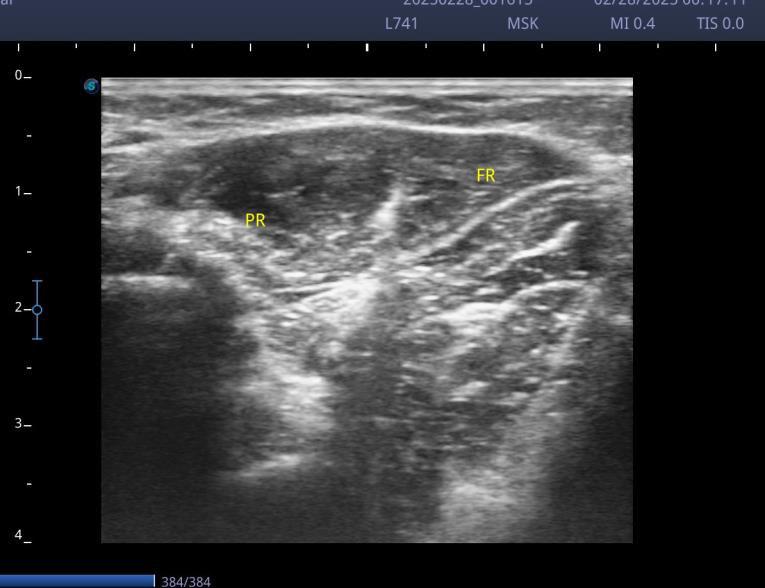

Case 2

Ultrasound-guided focal treatment with botulinum toxin in the

upper limb

TRICEPS BRACHII, 40 UI

PRONATOR TERES, 30 UI